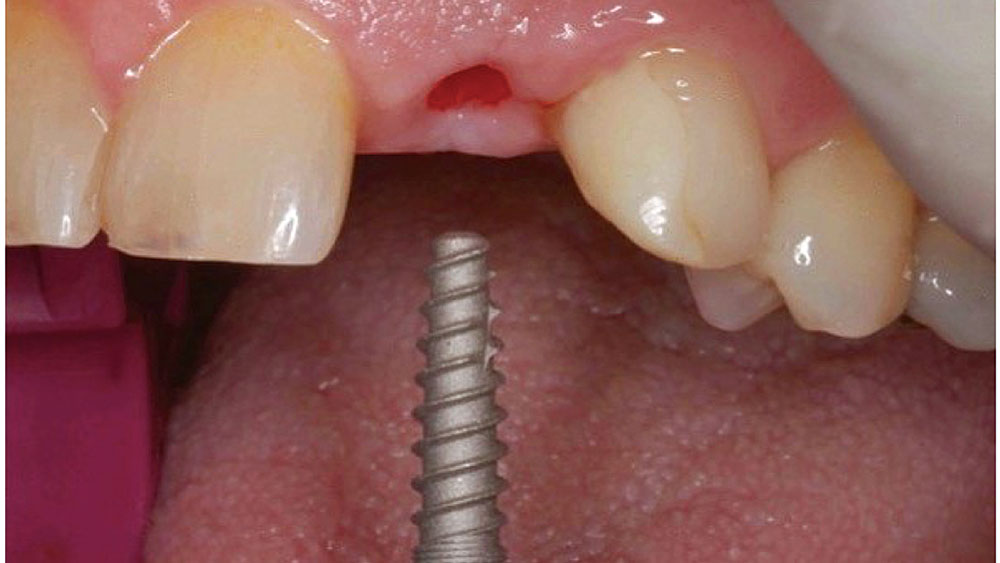

To achieve an optimal functional and esthetic outcome, the implant must be placed correctly with regard to trajectory, adjacent vital anatomy, and buccolingual, apicocoronal and mesial-distal positioning. Situating the implant so that the edges of the osteotomy are at least 2 mm from the buccal and lingual cortical plates, 2 mm from adjacent roots, 2 mm from vital structures, and 2–3 mm below the crest of tissue will keep the implant within the envelope of acceptability. The implant trajectory should emerge lingual to the incisal edge of the planned restoration, which allows for a screw-retained crown.

This case is an example of an ideal clinical situation for dentists who are new to placing implants in the esthetic zone. The patient requested treatment for a fractured upper lateral incisor. After extraction, grafting and healing, ample bone and soft tissue were present, and an implant was placed in optimal position for an esthetic result. The screw-retained restoration predictably restored form and function, illustrating the beautiful results that can be achieved by observing simple surgical and prosthetic guidelines.